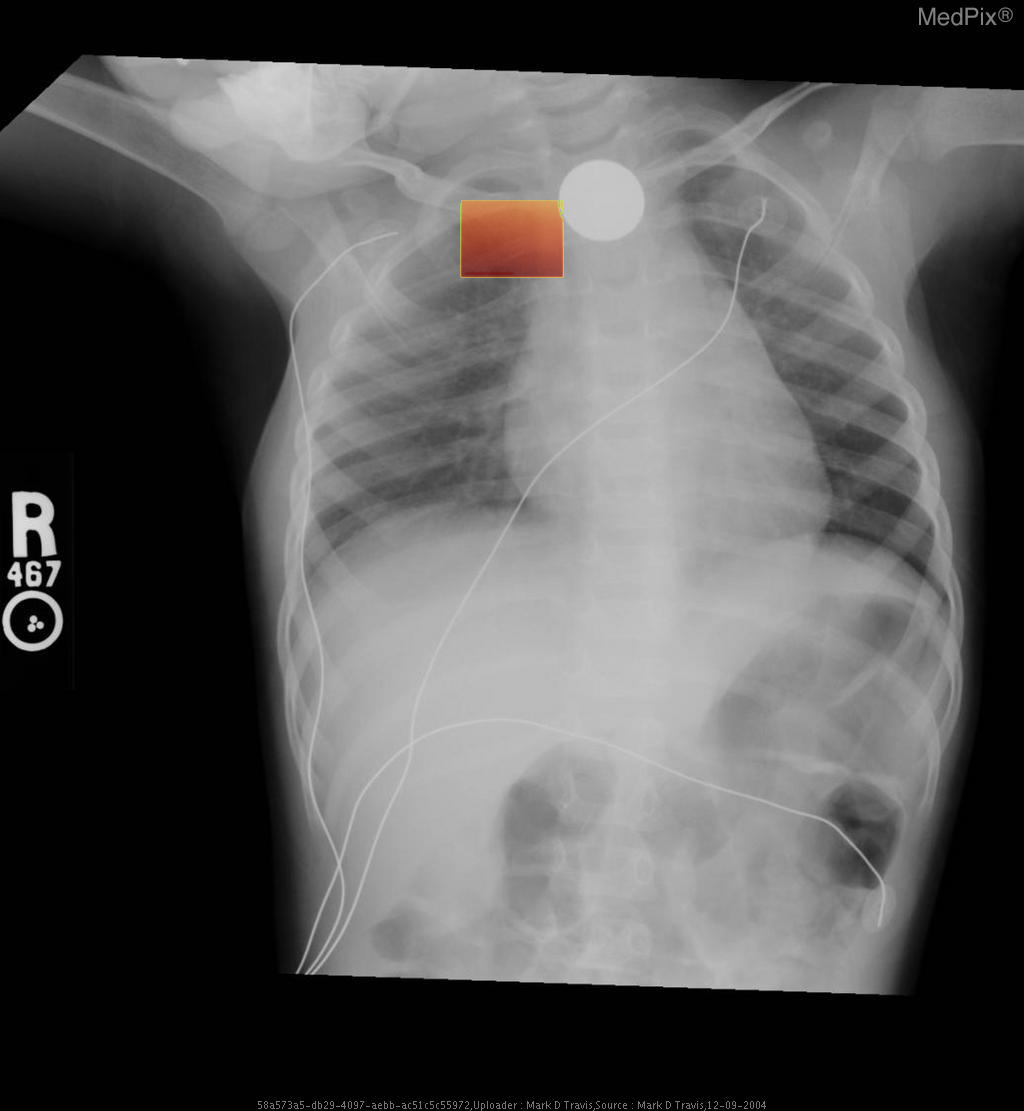

Esophageal foreign body - Coin ingestion

• Diagnosis: Esophageal foreign body

- Frontal chest and upper abdominal X-ray with standard orientation (image-left = patient-right).

- A well-circumscribed, round metallic density (coin) projects over the upper thoracic midline, posterior to the tracheal air column — typical of an object lodged in the esophagus rather than the trachea.

- No evidence of significant tracheal narrowing, suggesting airway is patent.

- Lung fields are clear bilaterally; no focal consolidation, effusion, or pneumothorax detected.

- Cardiothoracic ratio within normal range for age.

- Normal diaphragmatic contour and position; no subdiaphragmatic free air visualized.

- Enteric and monitoring tubes appear appropriately placed without complication.

2) Most likely diagnosis and why:

Esophageal foreign body (coin) lodged in the upper esophagus. The round metallic opacity centered over the thoracic midline and seen full-face on AP view indicates an esophageal (not tracheal) location—since tracheal foreign bodies appear more radiolucent and typically lie off-midline or show edge-on orientation. The absence of significant respiratory compromise supports esophageal lodging. Context consistency: Consistent — matches the provided context of “coin ingestion” in a pediatric patient. Confidence: 95%